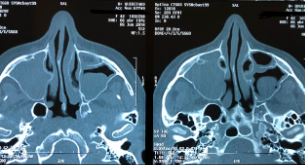

18

Q

¿Qué se ve en esta imagen?

A

Sinusitis Maxilo-Etmoidal Bilateral

Con hipertrofia de los cornetes y cornete medio paradójico